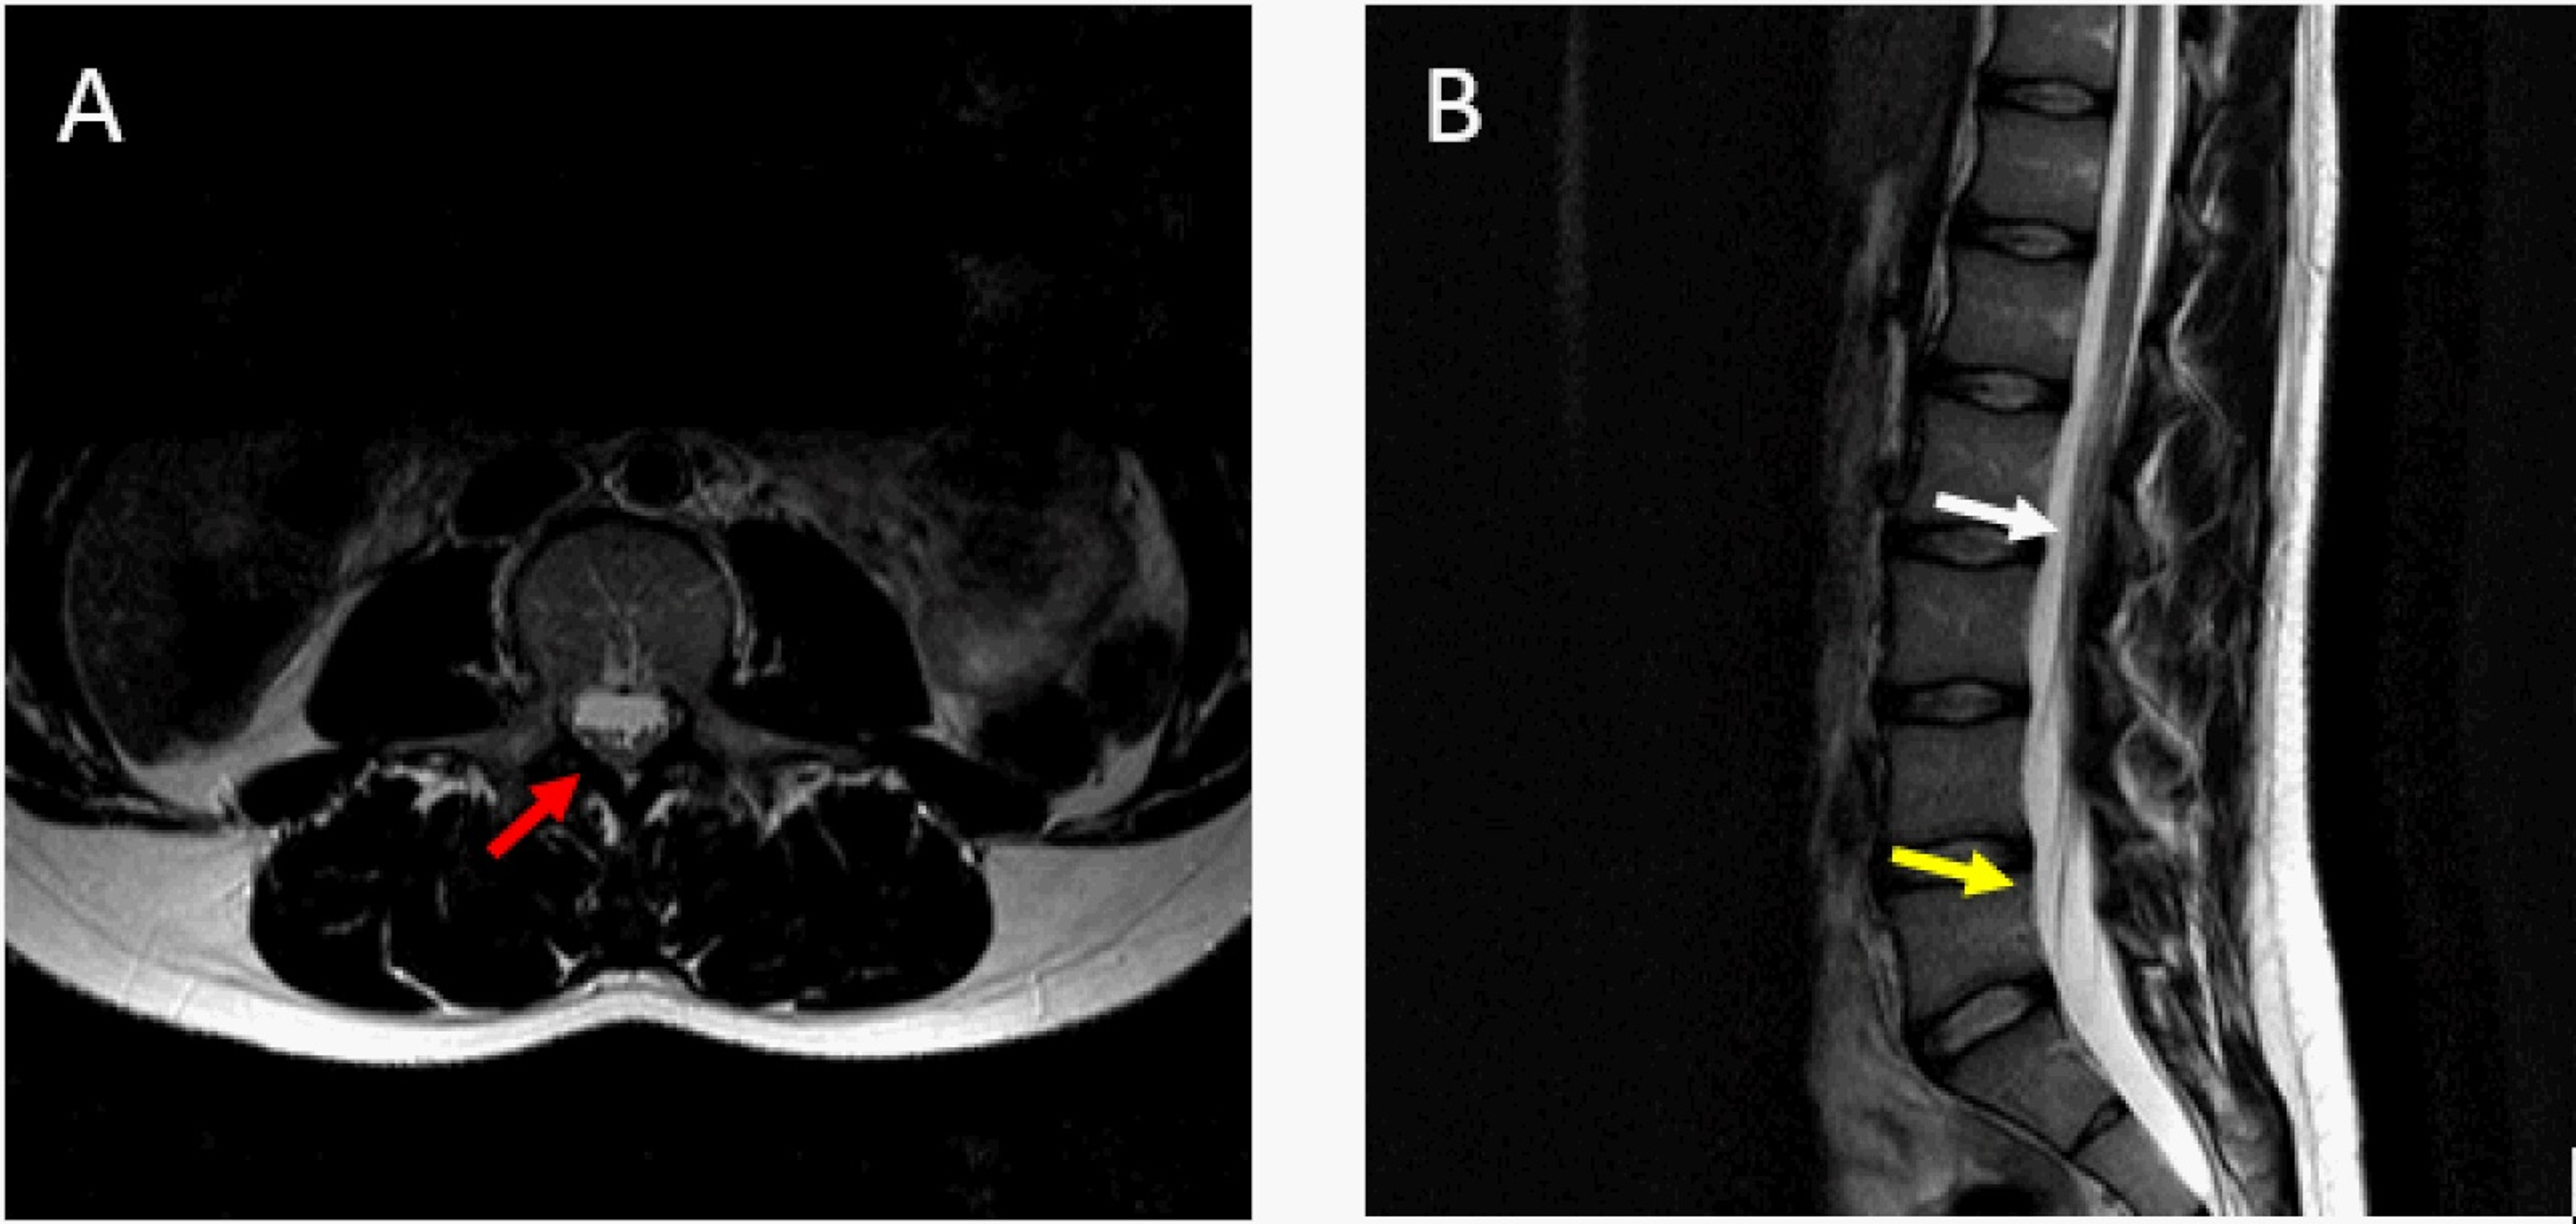

From neupsykey.com

Imaging of Tethered Spinal Cord Neupsy Key Tethered Spinal Cord Physical Therapy For many children, surgery to “untether” the spinal cord is the only treatment for tethered spinal cord. Treatment options for tethered spinal cord syndrome may include physical therapy, medication, surgical decompression, or a. Tethered spinal cord (tsc) is a rare neurological condition in which natural movement of the spinal cord within the spinal column is limited by. There are several. Tethered Spinal Cord Physical Therapy.